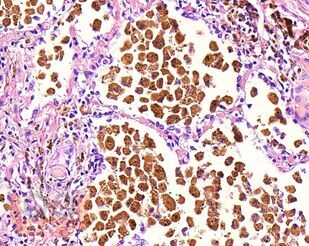

В учебном пособии представлен теоретический материал, перечень макропрепаратов и микропрепаратов, демонстрирующих типовые проявления патологических процессов. В цветных иллюстрациях и в описании микропрепаратов

сделан акцент на наиболее важных гистологических изменениях, позволяющих на светооптическом уровне диагностировать и дифференцировать состояния, отклоняющиеся от нормы, в том числе с использованием различных гистологических окрасок. Пособие помогает выделить главные аспекты изучаемых патологических процессов, организовать и конкретизировать учебный процесс.